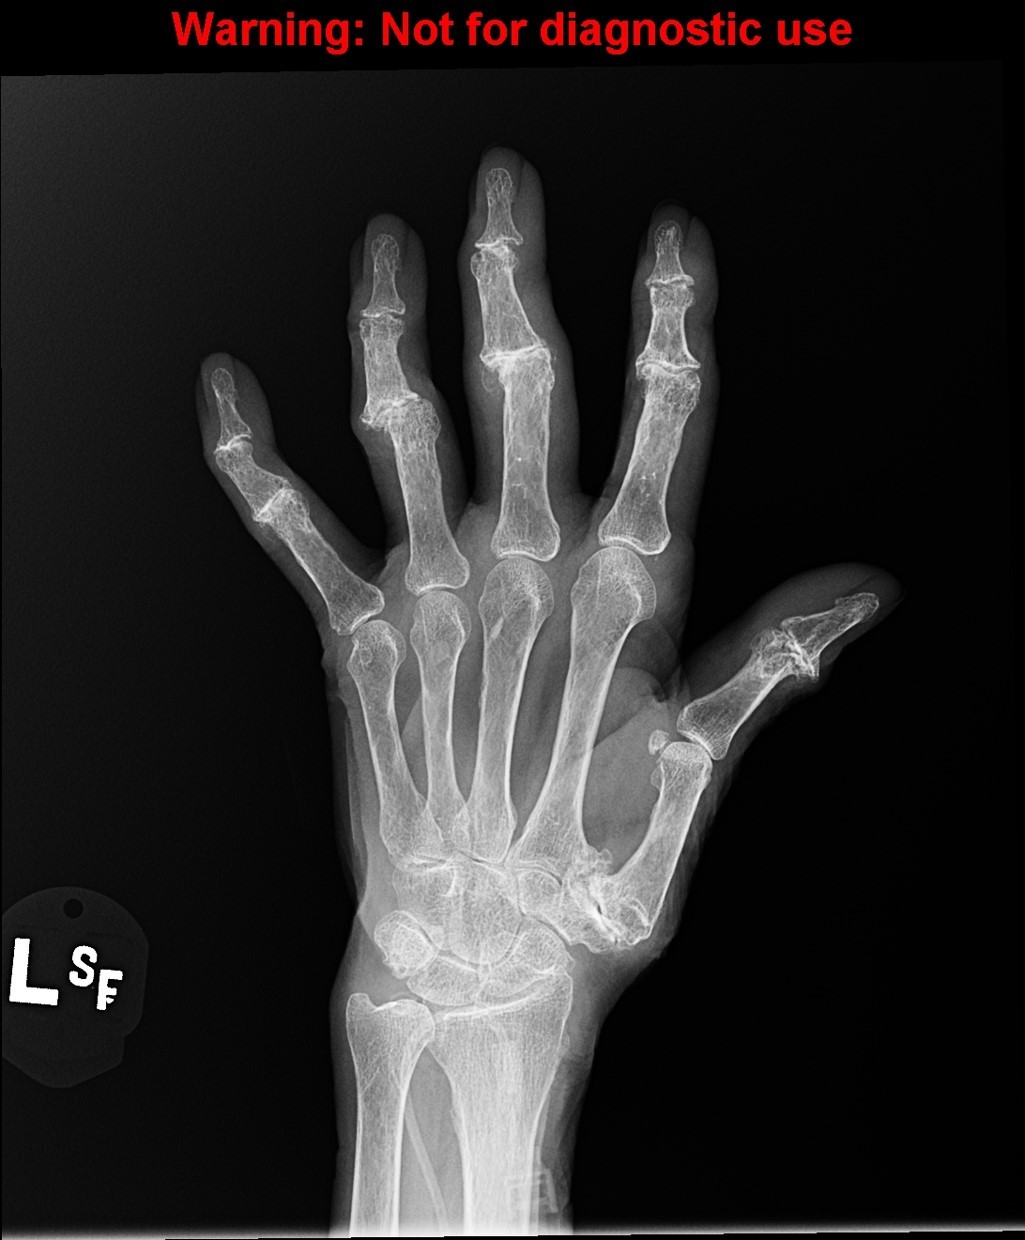

pencil in cup deformity

Psoriatic Arthritis

Almost always accompanies skin disease, especially nail changes

Mostly involves DIP joints of hands > feet